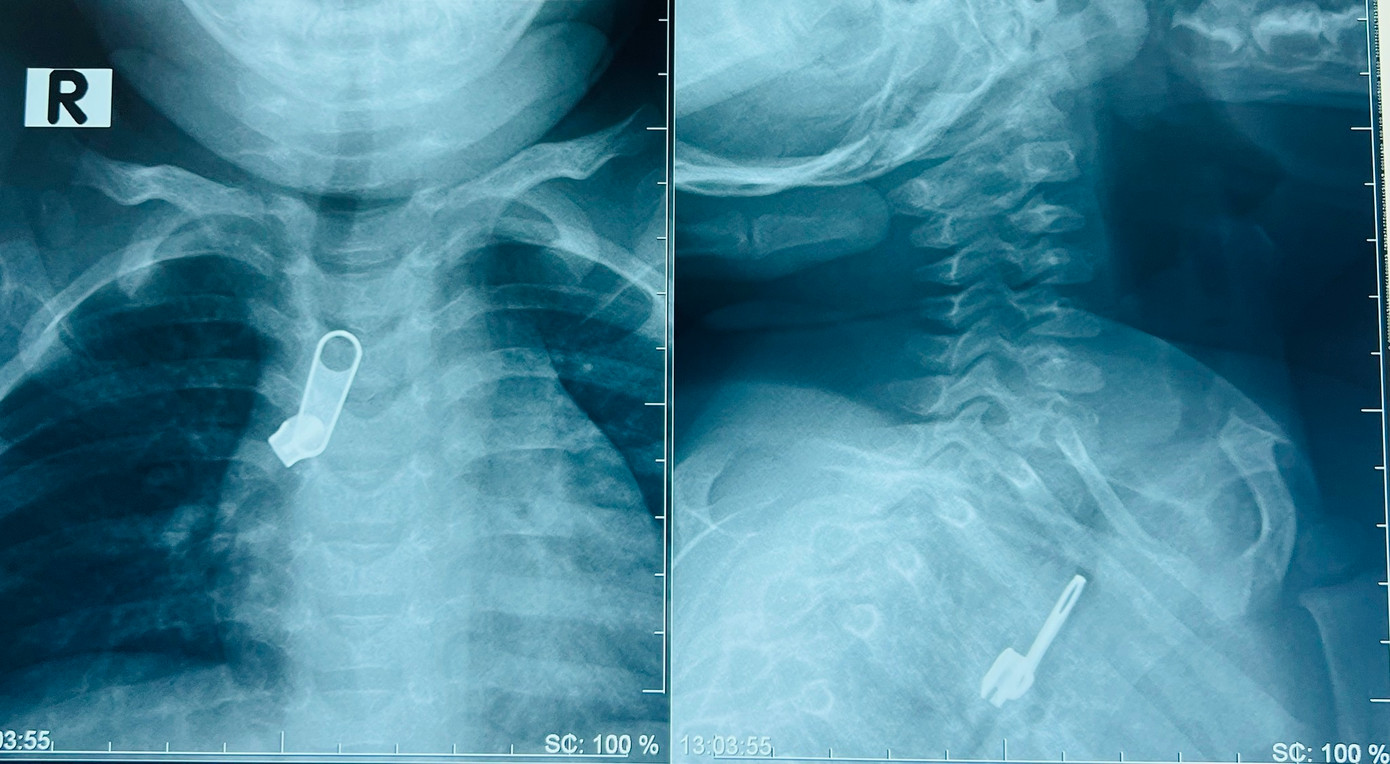

| Chiếc móc chìa khóa lọt vào đường thở khiến bệnh nhi phải nhập viện |

Tại đây, qua thăm khám và chụp X-quang bác sĩ phát hiện dị vật nằm phía trước cột sống ngực lệch phải, ngang mức đốt sống T3-T5 của bé.

Bệnh nhi nhanh chóng được chuyển đến khoa Tai Mũi Họng và chỉ định nội soi gắp dị vật. Sau khi gây mê, bằng thiết bị nội soi chuyên dụng cho trẻ, BS Lý Phạm Hoàng Vinh cùng ê kíp đã gắp thành công móc khóa kéo trong phế quản bên phải của bệnh nhi ra ngoài.